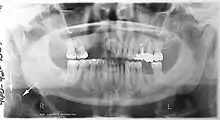

Orthopantomograms (OPTs) are used by health care professionals to provide information on:

- Impacted wisdom teeth diagnosis and treatment planning - the most common use is to determine the status of wisdom teeth and trauma to the jaws.

- Periodontal bone loss and periapical involvement.

- Finding the source of dental pain, and when carrying out tooth-by-tooth diagnosis.

- Assessment for the placement of dental implants

- Orthodontic assessment. pre and post operative

- Diagnosis of developmental anomalies such as cherubism, cleido cranial dysplasia

- Carcinoma in relation to the jaws

- Temporomandibular joint dysfunctions and ankylosis.

- Diagnosis of osteosarcoma, ameloblastoma, renal osteodystrophy affecting jaws and hypophosphatemia.

- Diagnosis, and pre- and post-surgical assessment of oral and maxillofacial trauma, e.g. dentoalveolar fractures and mandibular fractures.

- Salivary stones (Sialolithiasis).

- Other diagnostic and treatment applications.[2]